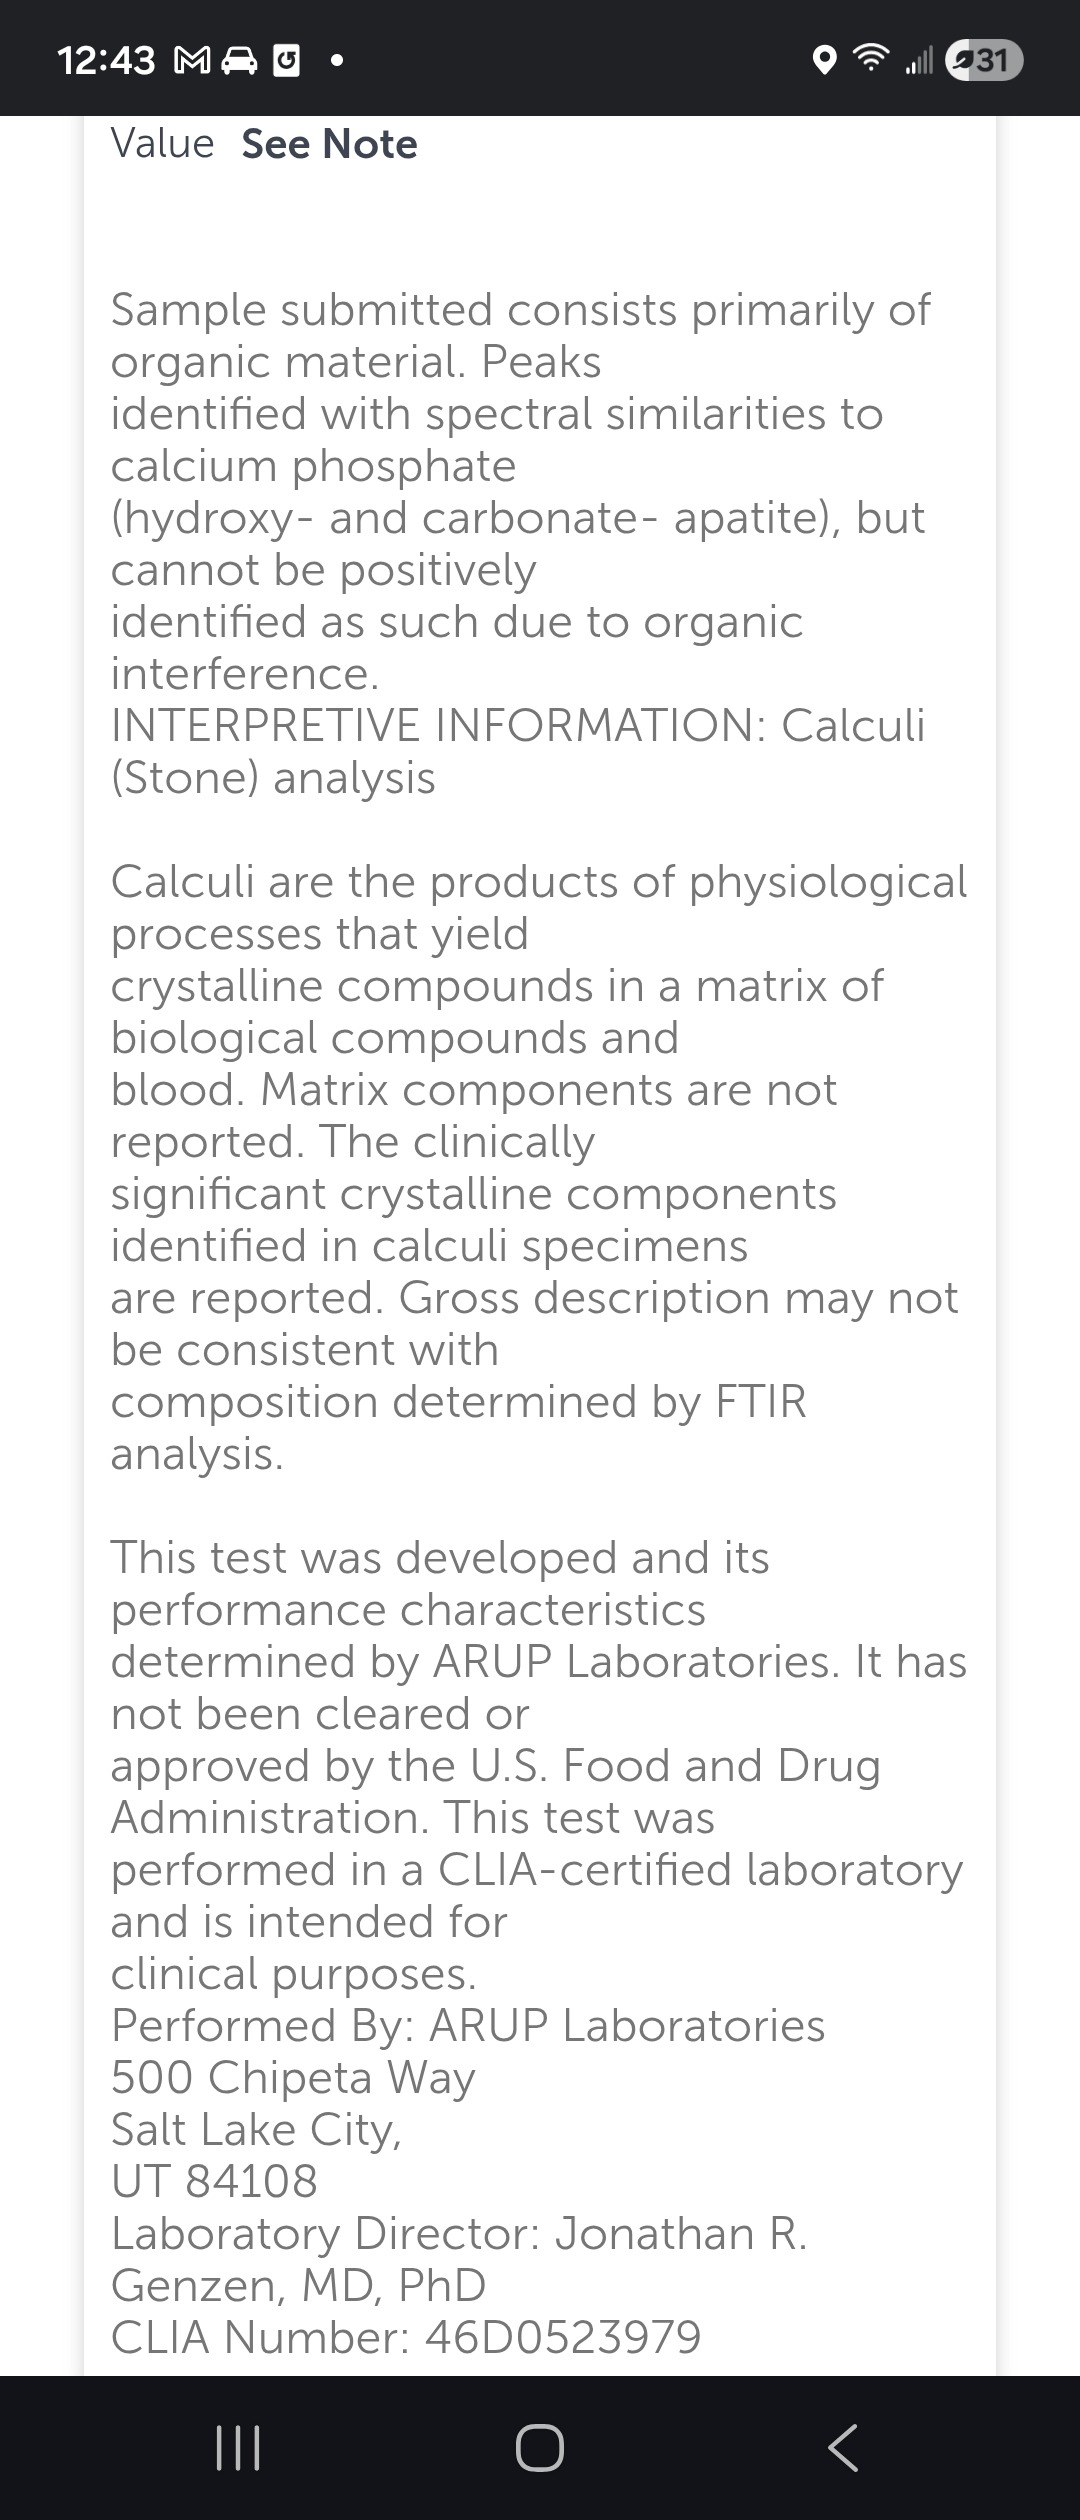

My fiancé and I are expecting our first child, and while this should be a time of excitement, we've been faced with unexpected challenges. My fiancé has been struggling with severe nausea, fatigue, and blood sugar issues due to her pregnancy, making it nearly impossible for her to work. On top of that, I recently developed kidney stones that required two surgeries, leaving me unable to work as the main breadwinner for our family.